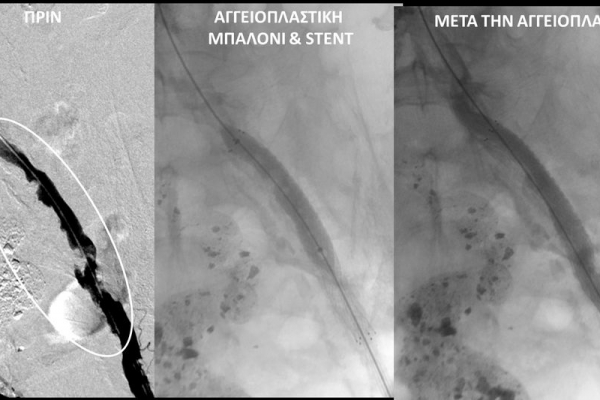

O σακχαρώδης διαβήτης είναι μεταβολική ασθένεια η οποία χαρακτηρίζεται από αύξηση της συγκέντρωσης του σακχάρου στο αίμα (υπεργλυκαιμία) και διαταραχή του μεταβολισμού της γλυκόζης. Ο βαθμός αύξησης της γλυκόζης στο αίμα και η παραμονή των αυξημένων τιμών της για μεγάλο χρονικό διάστημα βλάπτουν, κυρίως, τα μικρά αγγεία, προκαλώντας διαβητική νευροπάθεια, διαβητική νεφροπάθεια, αμφιβληστροειδοπάθεια κ.τ.λ., με σοβαρότατες συνέπειες σε πολλά όργανα-συστήματα.Στην Ελλάδα κάθε χρόνο πραγματοποιούνται 2.000 – 3.000 ακρωτηριασμοί κάτω άκρων, αφού το 4-5% των πασχόντων από διαβήτη εμφανίζει περιφερική αγγειοπάθεια με έλκη ή και γάγγραινα στα πόδια. Σε ποσοστό 80% οι ακρωτηριασμοί θα μπορούσαν να αποφευχθούν και η επεμβατική ακτινολογία μπορεί να βοηθήσει σημαντικά.Η διαδερμική ενδαγγειακή αγγειοπλαστική (percutaneous transluminal angioplasty, PTA) είναι μια ελάχιστα επεμβατική μέθοδος αντιμετώπισης των αρτηριακών στενώσεων ή και αποφράξεων του διαβητικού ποδιού (περιφερικήδιαβητικήαρτηριοπάθεια).